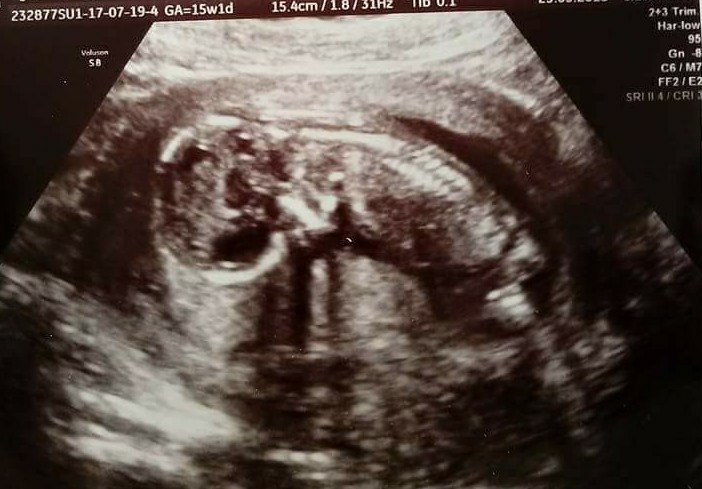

Wczoraj byliśmy na kontroli dzidziek rośnie, bryka, staje na głowie. Krwiaki się wchłonęły i okazało się, że Mateusz ma na imię :)

received_10215576681440192-1-1.jpg

• received_10215576681440192-1-1.jpg

63,8 KB · Wyświetleń: 1 371